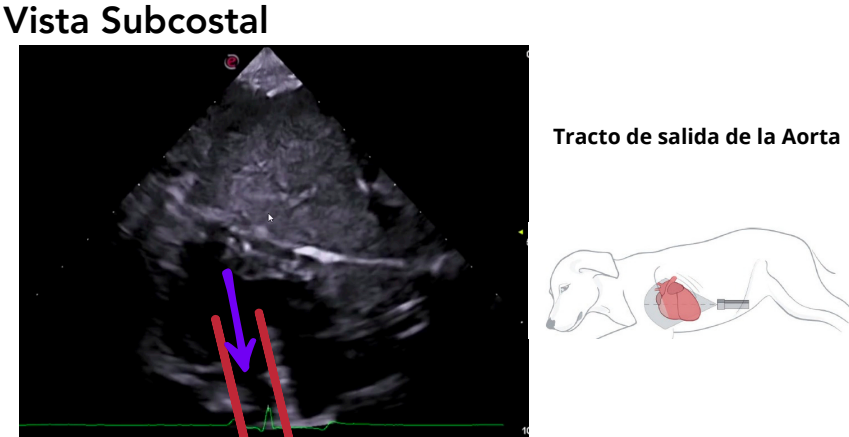

Vista subcostal (subxifoidea)

- Se accede a través de la apófisis xifoides.

- Se usa un transductor de baja frecuencia (2–2.5 MHz).

- Permite estudiar el tracto de salida del VI y la aorta ascendente.

- Alineación ideal para el Doppler, que mide velocidades en aorta.

Valores normales:

- 1.1–1.5 m/s (normal)

- >3 m/s: estenosis aórtica

- <1 m/s: CMD

Medición del flujo aórtico

Mide la velocidad con la que la sangre sale del ventrículo izquierdo hacia la aorta durante la sístole. Refleja cuán rápido y eficiente es el vaciado del ventrículo izquierdo y permite detectar obstrucciones al flujo o alteraciones en la contractilidad.